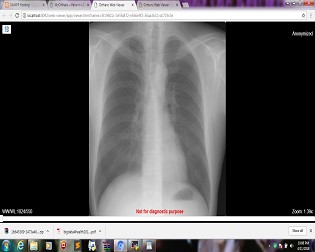

DICOM server based application

Radiology Data query and retrieve from an Orthanc instance